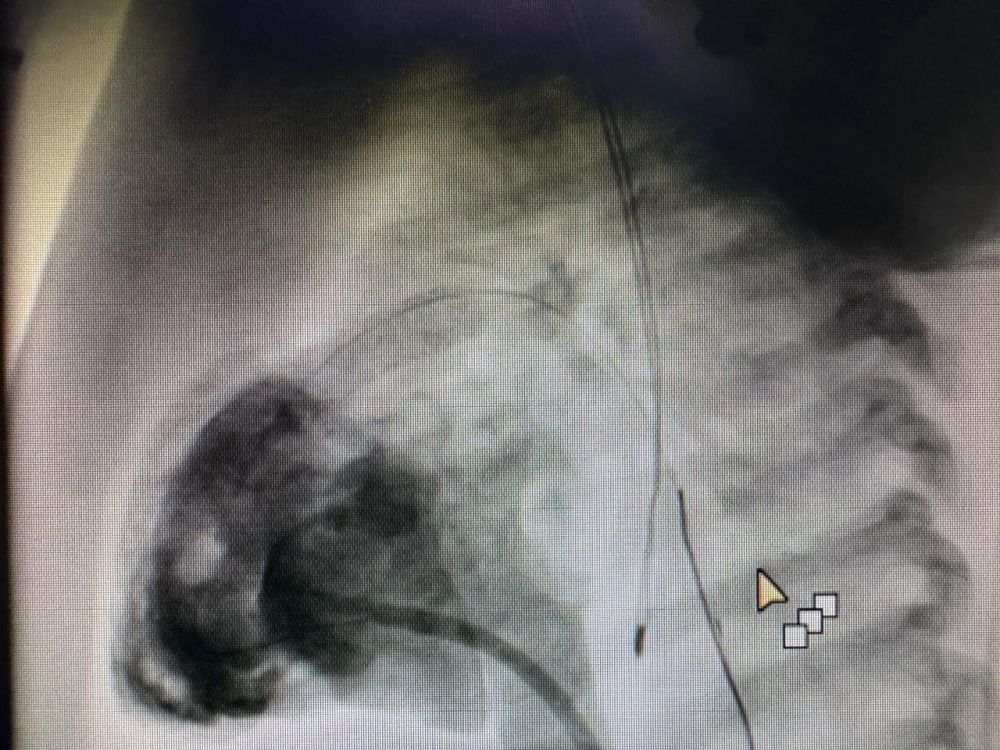

أشار التجمع أن الفريق الطبي قام بإجراء قسطرة قلبية تشخيصية وعلاجية بشكل عاجل، تضمنت زراعة دعامة شريانية لتوسعة الشريان الرئوي، في عملية استغرقت نحو 45 دقيقة وتكللت بالنجاح ولله الحمد، حيث ارتفعت نسبة الأكسجين لدى الطفل إلى ما بين 90-93%.

قسطرة تشخيصية وعلاجية

أشار التجمع أن الفريق الطبي قام بإجراء قسطرة قلبية تشخيصية وعلاجية بشكل عاجل، تضمنت زراعة دعامة شريانية لتوسعة الشريان الرئوي، في عملية استغرقت نحو 45 دقيقة وتكللت بالنجاح ولله الحمد، حيث ارتفعت نسبة الأكسجين لدى الطفل إلى ما بين 90-93%.